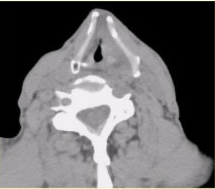

[单选题,案例分析题] 患者男,60岁,声音嘶哑半年,CT表现如下图。以下诊断正确的是()A .声门区喉癌B . 声门上喉癌C . 喉正常表现D . 喉结核E . 喉乳头状瘤F . 喉憩室

[多选题,案例分析题] 患者男,60岁,声音嘶哑半年,CT表现如下图。有关喉癌,正确的表述是()A .喉癌以鳞癌多见B .声门上区淋巴结转移最常见,声门下区次之C .声门区喉癌好发于声带后1/3与中1/3的交界处D . D.喉癌诊断中最重要的内容之一为评价前联合有无受累E .CT仿真内镜可清晰显示声门区病变F .喉癌以腺癌多见

[多选题,案例分析题] 患者男,60岁,声音嘶哑半年,CT表现如下图。有关咽腔划分,正确的表述是()A .分为鼻咽、口咽和喉咽B . 喉软骨包括甲状软骨、环状软骨和会厌软骨C . 喉腔可分为声门上区、声门区和声门下区D . 室带位于声带下方E . 双侧梨状窝可不对称F . 下咽癌包括梨状窝癌、环后癌及咽后壁癌